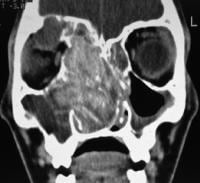

Relevant anatomy is the same as in any endoscopic sinus surgery procedure. Often, anatomy is distorted because of expansion of the sinuses secondary to the disease process. The lateral nasal wall is pushed medially, obliterating the nasal cavity on the affected side, and the inferior and middle turbinates are pushed inferomedially, as depicted in the 1st two images below. If the ethmoid sinuses are involved, the roof often is expanded superiorly into the anterior cranial fossa, and the lateral wall is expanded into the orbit, as depicted in the last image below.

A 9-year-old girl with allergic fungal sinusitis dA 9-year-old girl with allergic fungal sinusitis displaying telecanthus and asymmetrical positioning of her eyes and globes.Coronal CT scan showing extensive allergic fungal Coronal CT scan showing extensive allergic fungal sinusitis involving the right side with mucocele above the right orbit and expansion of the sinuses on the right.Typical view of a middle meatus in a patient with Typical view of a middle meatus in a patient with allergic fungal sinusitis with expansion of the ethmoid complex and extension of the middle turbinate more inferiorly. This is a postoperative view.